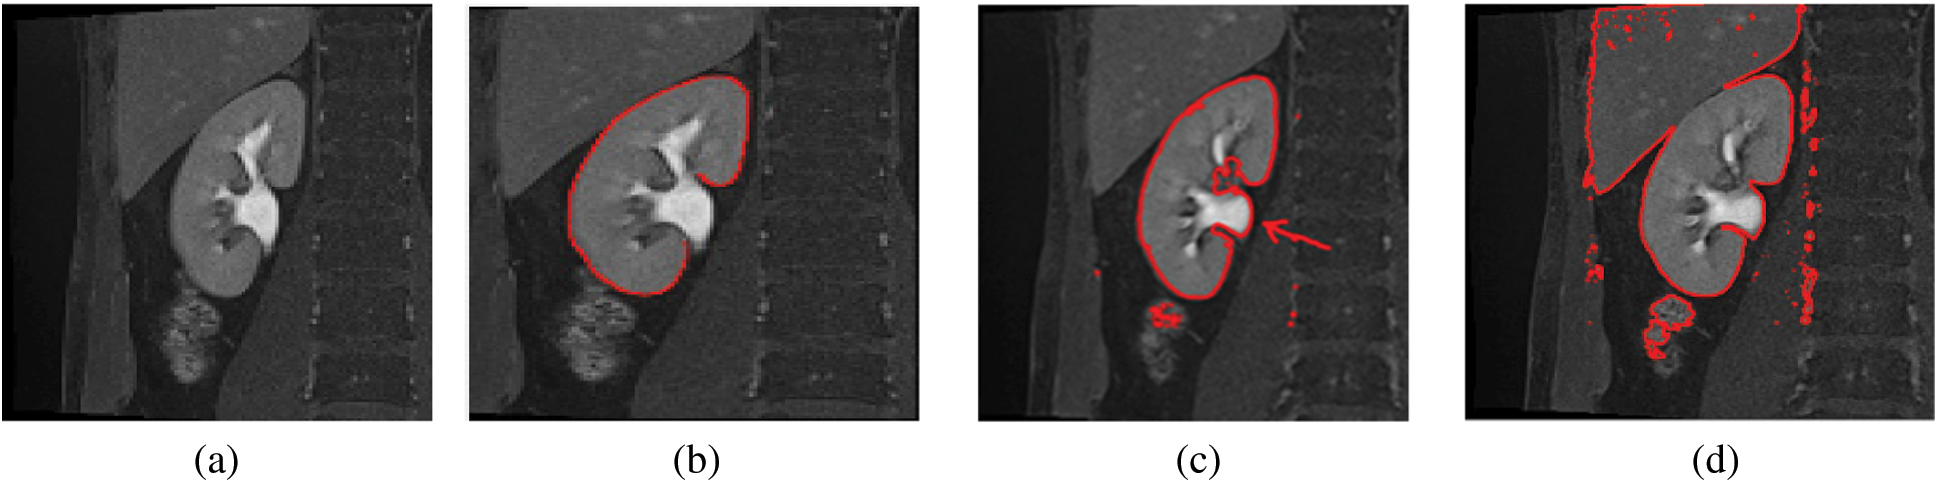

The MRI image acquisition could result in varying image contrast qualities and image artifacts, which degrade the quality of the captured image. Therefore, the efforts to improve the image contrast quality will enhance the performance of the whole imaging system, and provide valuable information for the diagnosis and treatment processes. During kidney segmentation, as shown in Fig. 1, the precise and correct segmentation of kidney edges is important for many applications associated with surgical planning and diagnosis (Fig. 1b). The inaccurate segmentation occurs due to the complex tissue environment surrounding the kidney, including the renal column (Fig. 1c), and liver, which have the same intensities due to low image contrast (Fig. 1d). Thus preprocessing of kidney MRI scans is an important procedure to enhance the image contrast which may lead to a better kidney segmentation. The internal structure of the kidney is complex and difficult to recognize. Several neighboring tissues or organs, including the renal column (Fig. 1c), muscles, and liver have the same intensities (Fig. 1d). The varieties of kidney shapes (in terms of length and volume) and the captured image contrast complicates the segmentation of the kidney. It is therefore evident why the kidney segmentation methods may not perform well. This motivates us to propose a new enhancement model for kidney MRI scans which improves the segmentation performance and accuracy. The proposed model must perform the segmentation process accurately to detect the kidney boundary and eliminate the unwanted structures of nearby regions (e.g., renal column, muscles, and liver) that share the same properties as the kidney (e.g., in intensity). This study is prepared as follows: The related work introduced in Section 2. Section 3 describes the proposed model. Section 4 discusses the experimentation results. Finally, Section 5 concludes the study.

Figure 1: Sample images showing the results of automatic segmentation of kidney MRI scans. (a) The original image, (b) Correctly-segmented kidney, (c) Inaccurate segmentation, with the renal column (arrow), (d) Inaccurate segmentation, with the liver